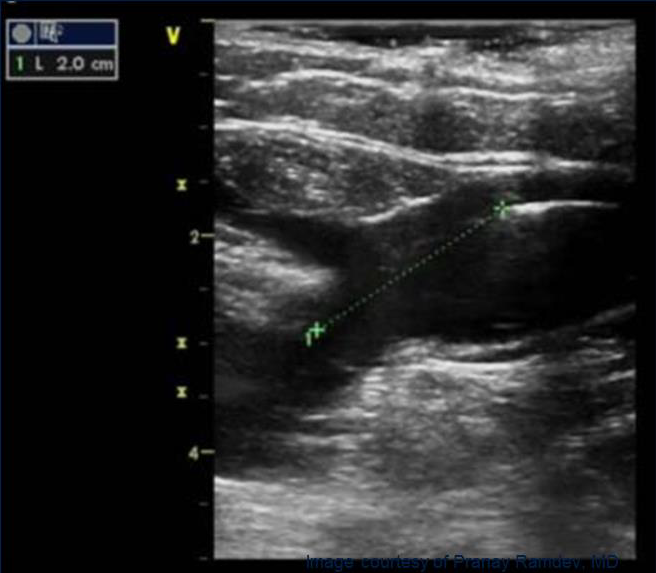

Предоперационная разметка на УЗИ

• Сафено-феморальное соустье

• Глубину залегания вены (< 10 мм от поверхности кожи)

• Минимальный и максимальный диаметры вены

• Особенности анатомии - Извилистые и расширенные сементы, Удвоение вены, Притоки, Ветви и перфоранты

• Места возможного доступа